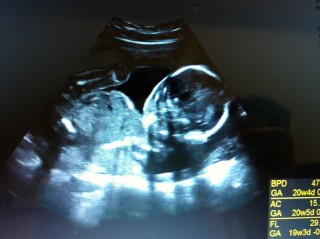

写真:20w3d:ともちゃんさん

出血したり腹痛があったりと、ずいぶん心配しましたが、344gと週数通りの大きさになっていました! 普段はグーにしているお手ても、両手をパーに広げてくれました。指もしっかり出来ていることに感動。今回お顔は見せてくれませんでした。